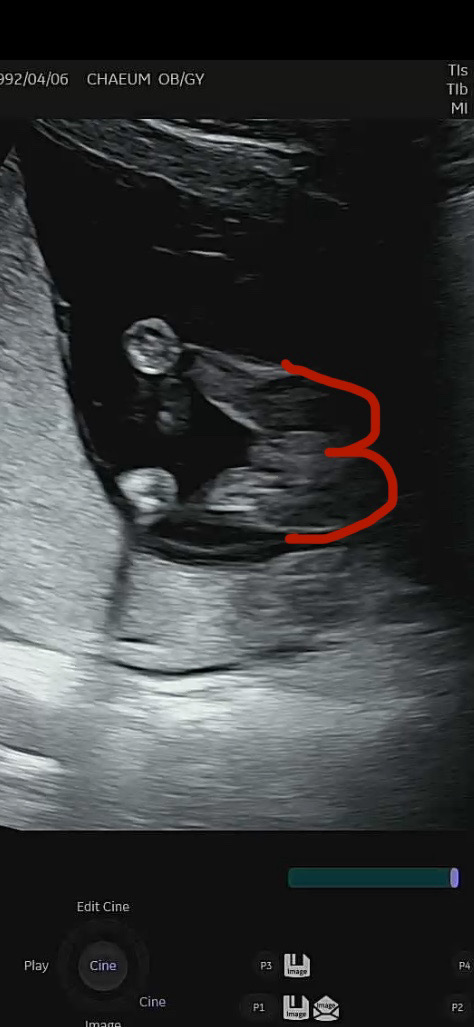

14주 성별 궁금해요!!

선생님은 아직 아무것도 안보여서 딸인거같다고 하셨는데 다음 초음파때 더 정확히 보자고 하셔서요 ㅎㅎㅎ 가운데 살짝 뭉툭하게 나와있는거같기도 하고.. 헷갈리네요